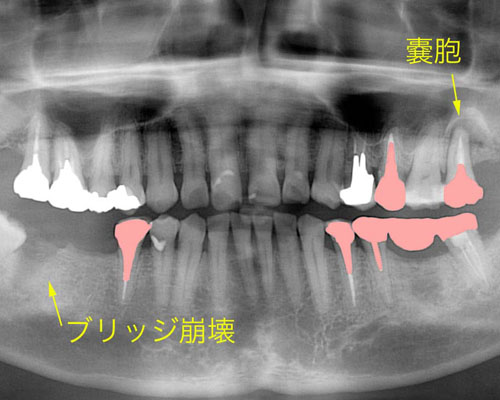

右側下(写真では左)にブリッジを入れていたのですが、歯が割れて抜いたとのことでした。左上にはのう胞といって膿の袋ができています。患者さんのご希望は、インプラントでした。年齢も50台ですので入れ歯は入れたくないとのことでした。

やっと右下にセラミックの歯が入りました。左上にも3本目のインプラントを入れ、もう1本の割れた歯を抜きました。しかし、レントゲンをよく見てみると左側を酷使していた為か、ブリッジの下に虫歯ができて怪しくなっています。

ここで振り返ってみましょう。最初に来院された時に失っていた右下に加え赤い部分が治療途中でどんどん壊れていった歯です。よく見て下さい。共通点があるのがお分かりいただけますか?そう、やり直した歯は全て神経を取った歯で、そのうち割れてしまったのは長い金属の心棒が入ったものです。